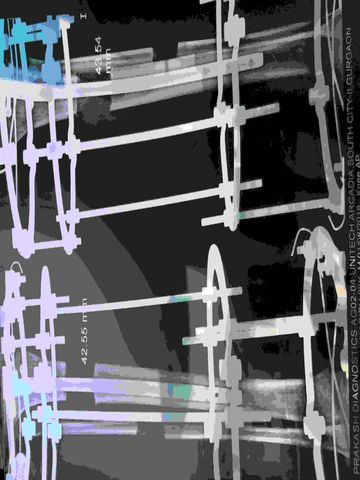

Lengthening Over Nail

Lengthening And Then Nailing

Precice Nail Lengthening

Precice Stryde Nail Lengthening

Cosmetic Limb Lengthening Surgery India

Limb Lengthening Surgery India